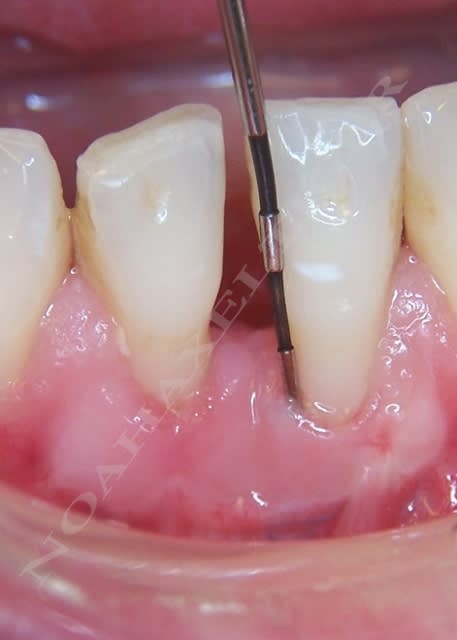

Initial ctkv65 - Eugenol

Initial t897lc - Eugenol